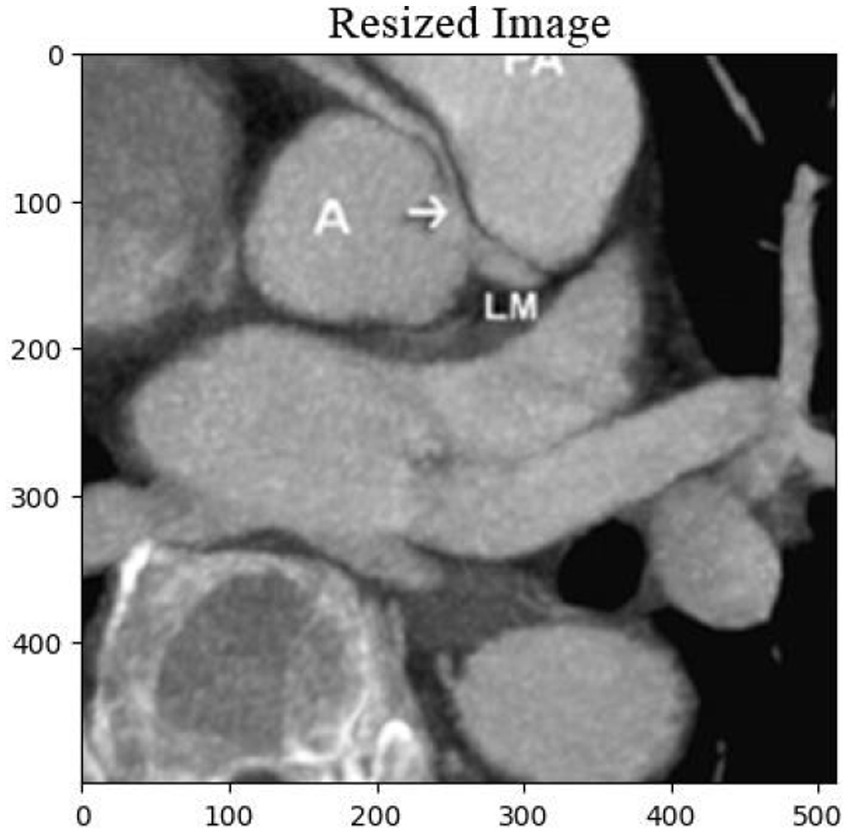

The cardiac CT Input Image is shown in Figure 4. In the preprocessing stage of cardiac CT image analysis, the initial step involves resizing the input images to a standardized dimension of 64 pixels by 64 pixels. This resizing procedure is crucial to establishing a uniform and manageable input size for subsequent analysis. Standardizing the image dimensions not only aids in computational efficiency but also ensures consistency in the input data fed into the analytical models. A 64 by 64-pixel resolution is likely driven by a balance between maintaining sufficient image detail for meaningful analysis and minimizing computational resource requirements. By establishing this standardized input size, the subsequent stages of image processing and feature extraction can be conducted with a consistent and optimized foundation, facilitating robust and reliable cardiac CT image analysis. Resized Input Image is shown in Figure 5.

Figure 5

Resized cardiac CT image with dimensions of 64×64 pixels, prepared for further image analysis and feature extraction. This step ensures uniformity across the dataset for optimal processing.